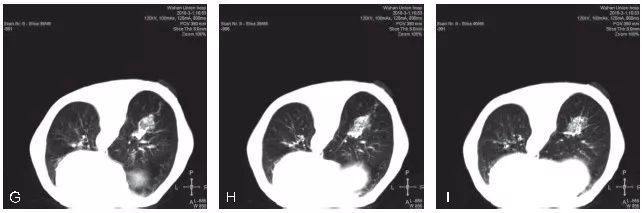

不良事件的发生率在可接受范围内。气胸是经胸廓细针穿刺活检最常见的并发症,发生率为16.0%~51.8%。在341位患者中,只有7位患者需要留置胸腔引流管。咯血发生率为8%~23%,没有患者需要治疗。从穿刺技术层面上来看,GGO的穿刺活检与普通肺结节的穿刺活检基本类似,同样需要注意避免引起气胸或出血的危险因素,从总体诊断效能及并发症发生情况来看,与普通肺结节大体一致。但也有部分研究者认为,GGO本身为经皮肺穿刺活检发生出血的一个危险因素,分析其可能的原因主要是GGO的体积通常较小,在使用全自动活检枪进行切割式活检时会损伤到更多的肺组织及肺内血管,造成较为明显的肺内出血。我院完成的GGO穿刺活检同样表现为较为明显和广泛的肺内出血征象(图5-2~图5-4)。这一点在小结节的穿刺活检中同样经常出现。因此,我们要求对于小结节/GGO的穿刺活检,务求“一击必中”。因活检取材易出现较明显的肺内出血征象,如取材不满意,即使再次进行CT扫描,亦可能无法为我们提供有效的影像引导,导致最终无法进行有效的调整,导致活检取材失败。

图5-2 A~C. 显示患者右肺下叶后基底段mGGO,选取俯卧位进行穿刺活检;D~F. 显示穿刺活检的实时CT影像,选取最短的穿刺路径,并尽量使同轴穿刺针与较粗大的肺内血管平行。图中显示同轴穿刺针到达预设位置,并未紧邻靶结节表面,为活检预留好空间,以免损伤该结节远端的肺内血管;G~I. 显示完成活检后,拔除同轴穿刺针。再次进行CT扫描,见靶结节活检区域明显的肺内渗出性改变,提示较严重的肺内出血。病理结果示:(右肺)浸润性腺癌